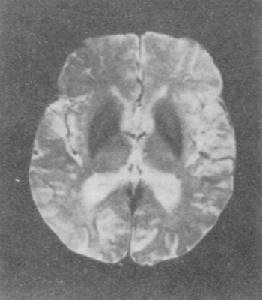

④血及腦脊液常規檢查無異常,CT、MRI檢查也無特徵性所見。

②血管性:多發性腦梗死病史、假性球麻痹、腱反射亢進、病理征和神經影響學檢查等可提供證據;